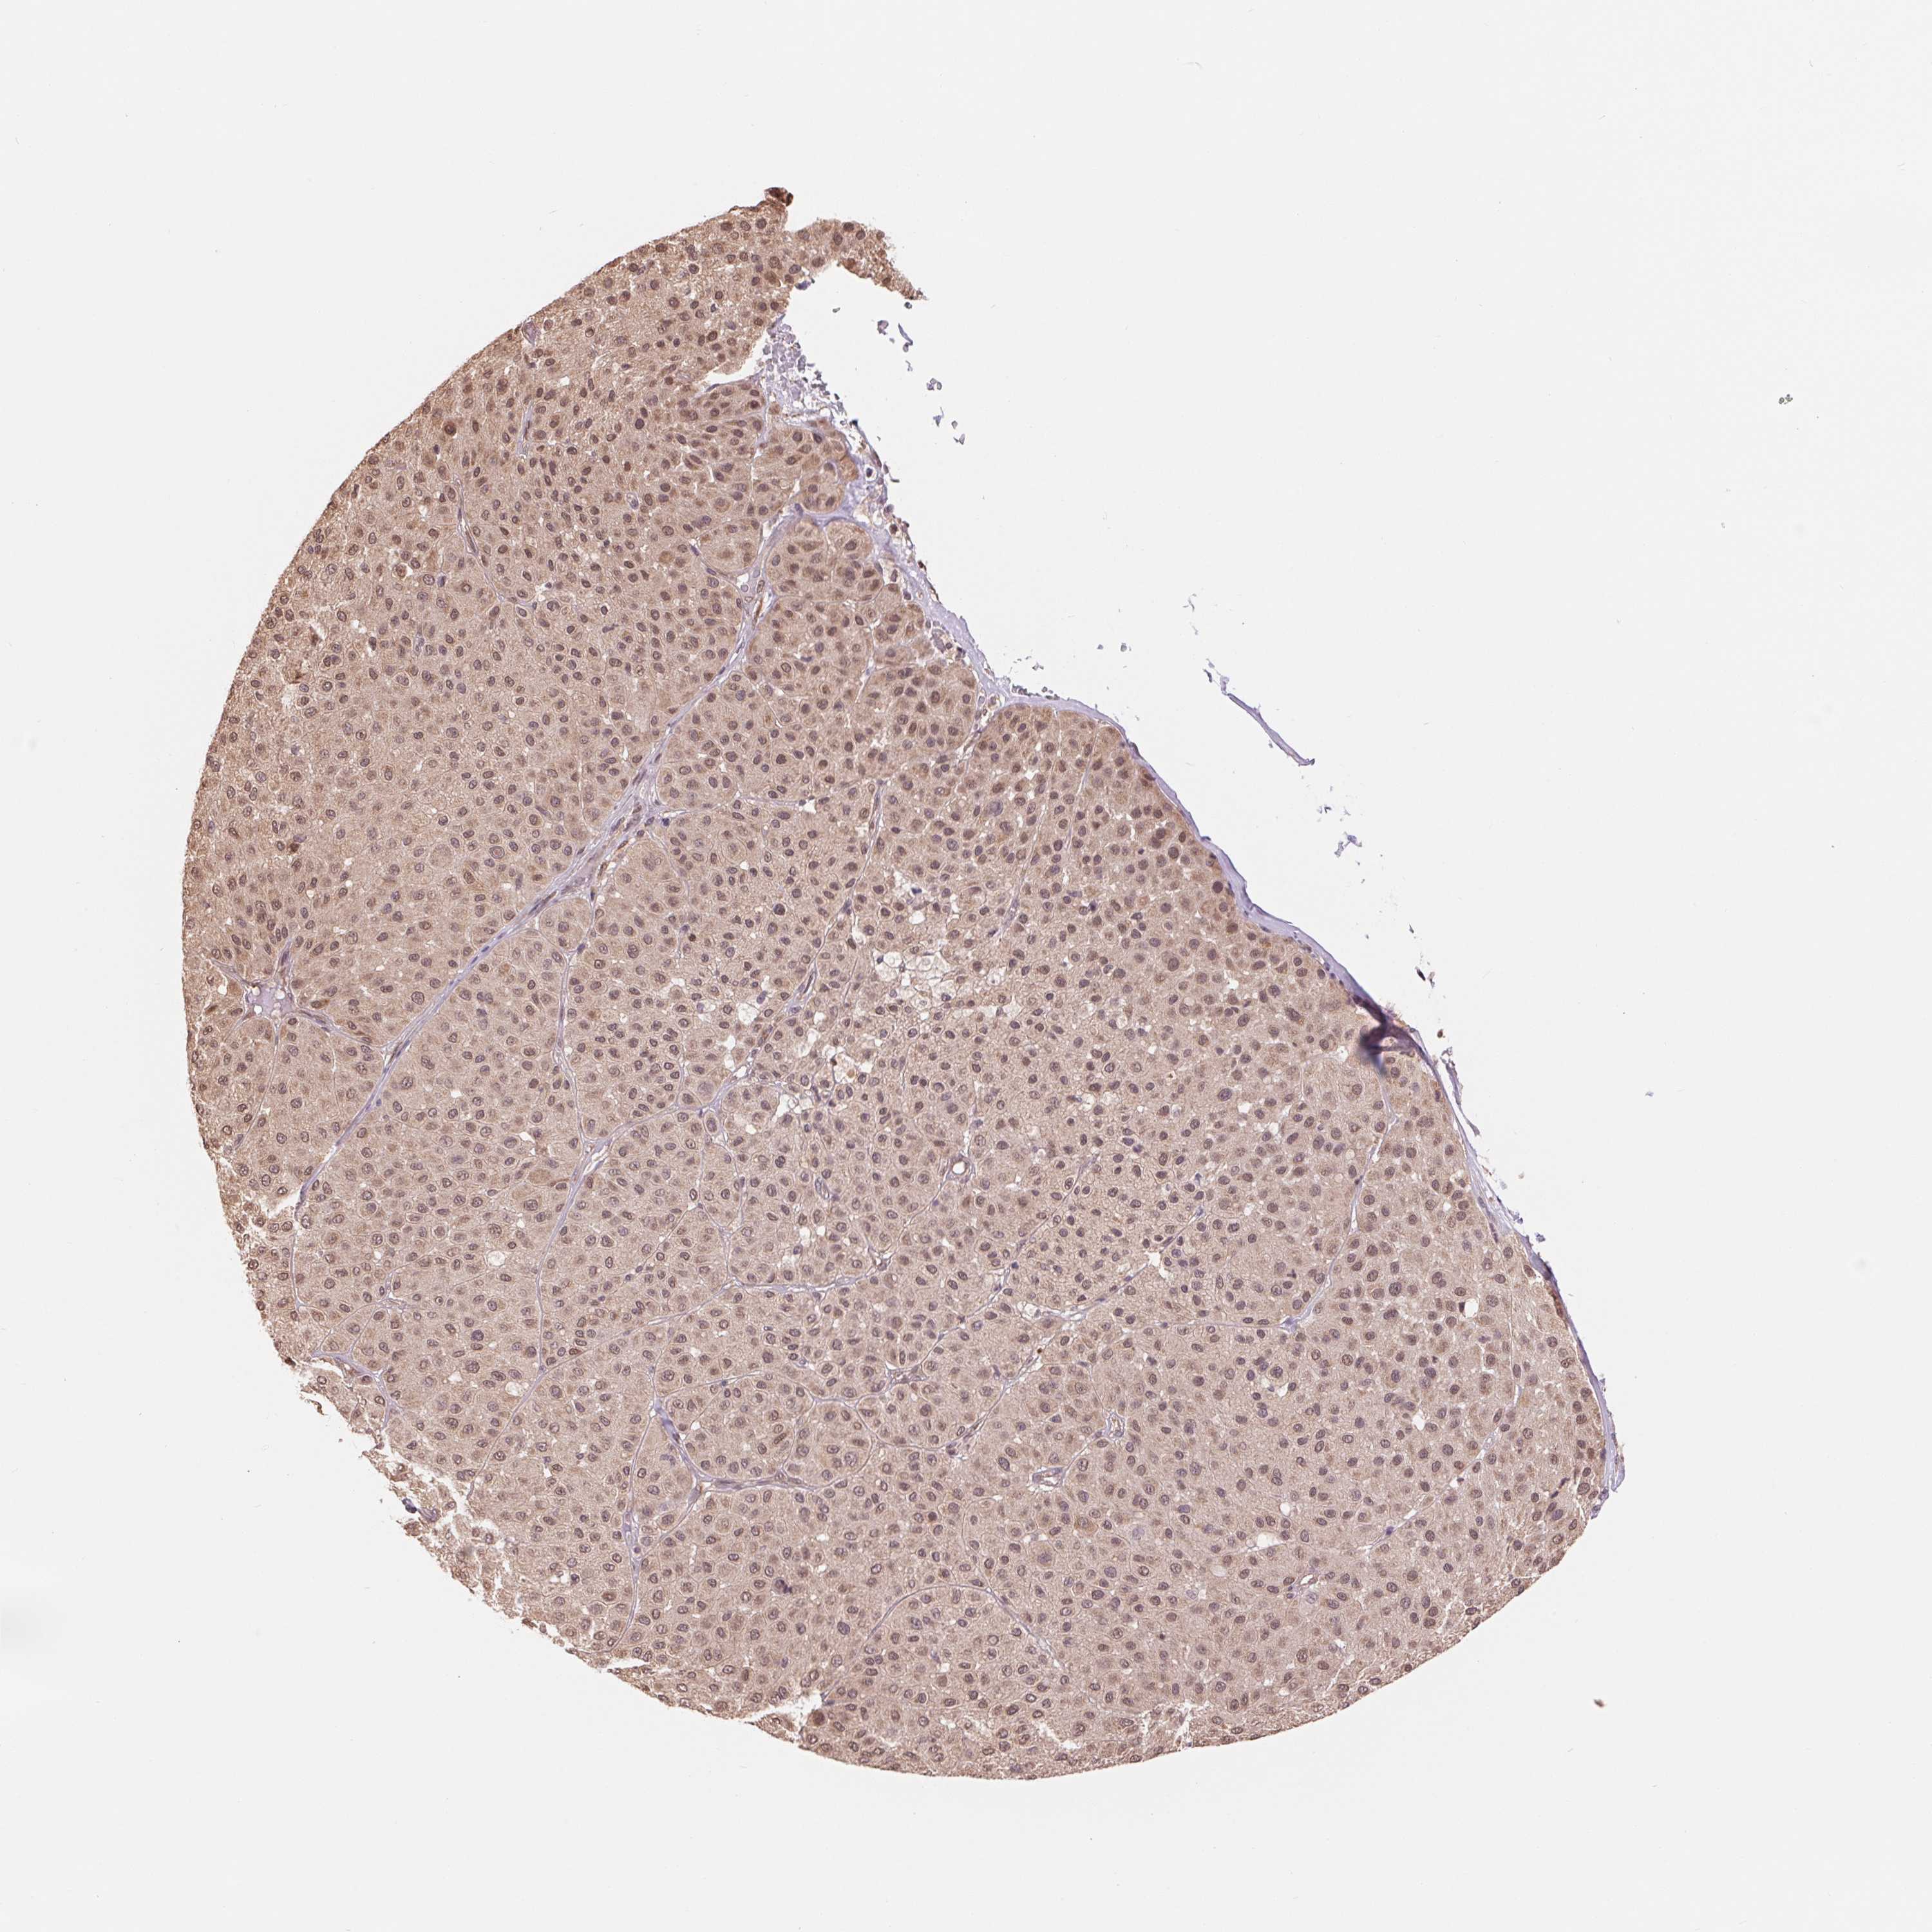

MELANOMA - Protein expressioni

A mouse-over function shows sample information and annotation data. Click on an image to view it in a full screen mode. Samples can be filtered based on level of antibody staining by selecting one or several of the following categories: high, medium, low and not detected. The assay and annotation is described here.

Note that samples used for immunohistochemistry by the Human Protein Atlas do not correspond to samples in the TCGA dataset.

Antibody stainingi

Antibody staining in the annotated cell types in the current human tissue is reported as not detected, low, medium, or high, based on conventional immunohistochemistry profiling in selected tissues. This score is based on the combination of the staining intensity and fraction of stained cells.

Each image is clickable and will lead to virtual microscopy that enables deeper exploration of all samples and also displays staining intensity scores, fraction scores and subcellular localization as well as patient and tissue information for each sample.

Antibody HPA058166

Staining

High

Medium

Low

Not detected

Intensity

Strong

Moderate

Weak

Negative

Quantity

>75%

75%-25%

<25%

None

Location

Nuclear

Cytoplasmic/membranous

Cytoplasmic/membranous,nuclear

Malignant melanoma, NOS

Malignant melanoma, Metastatic site